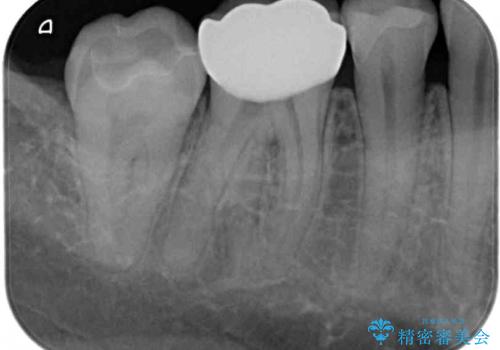

通常の咬み合わせ位置と比較して、上顎の歯列が全体的に前方にある状態で、上下前歯の前後方向の位置に著しい差がありました。

上顎奥歯付近にアンカースクリューを用い、上顎歯列全体の後方移動と、大臼歯圧下を促し、前歯の上下関係を改善することとしました。